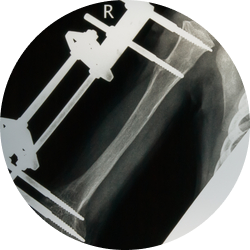

Хирургическое лечение делают после тяжелых травм и механических повреждений, приводящих к перелому костей. Костные фрагменты фиксируются специальные конструкции, сделанные из титана, керамики, разнообразных сплавов (кобальт-хром-молибденовый) и иных гипоаллергенных материалов. В зависимости от клинической ситуации, давности перелома, возраста пациента, наличия сопутствующих патологий применяют внутренний (погружной) внутрикостный или накостный остеосинтез с использованием винтов, пластин, штифтов, чрескостный (наружный) с помощью компрессионно-дистракционных устройств, например, аппарата Илизарова или комбинированный вариант остеосинтеза.

С помощью титановых конструкций разного размера (винты, штифты, пластины) специалист проводит фиксацию кости, предотвращая их последующее смещение и обеспечивая правильное сращение. В зависимости от диагноза необходимые стабилизирующие крепежи располагаются на поверхности костных структур (накостный, экстрамедуллярный остеосинтез) или внутри канала кости (внутрикостный, интрамедуллярный остеосинтез). В некоторых случаях ставится внешний аппарат Илизарова (наружный остеосинтез), состоящий из спиц, проводимых через отломки костей, и скоб или колец, которые размещают снаружи.